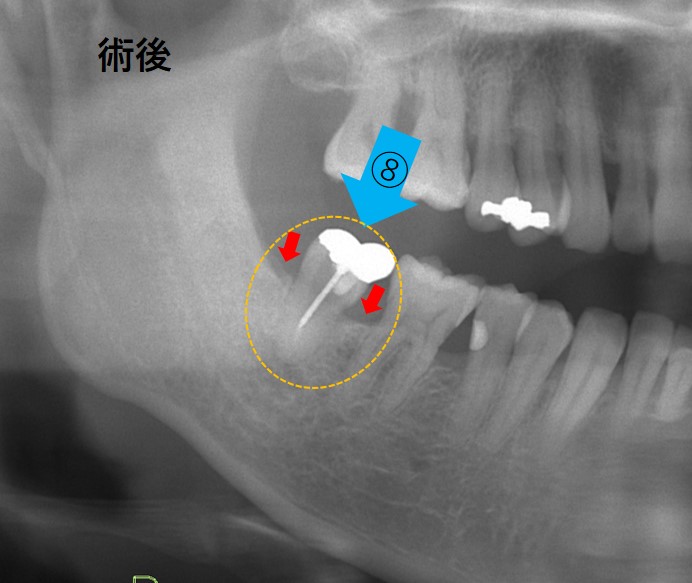

移植後2年以上経過した写真です。

赤の矢印部分に骨が再生していることが確認できます。

なぜ骨が吸収してしまった部分に骨が再生するのでしょうか。それは、移植した親知らずの周りに厚さ30ミクロンの薄い歯根膜という組織があります。それが下写真です。赤くなっている部分が歯根膜です。ここに「歯根膜細胞」があります。歯根膜細胞は骨芽細胞という細胞に分化して、周囲に骨を再生させるのです。

この歯根膜があるからこそ失われた骨が再生するのです。